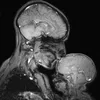

@doctorhoeflinger: Learn the steps that a Brain surgeon uses to expose the human brain #medicalstudent #doctor #LearnOnTikTok #fypシ